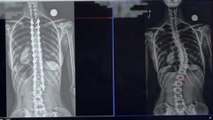

Serena Nye, 24, was told after her 20-week pregnancy scan her unborn son had spina bifida.

It meant his spine and spinal cord was not developing properly, causing a gap in his spine, leaving at high risk of weakness or total paralysis of his legs.

So in an incredible operation, doctors took Serena's womb OUT of her body, at 26 weeks, to operate on her unborn son's spine via keyhole surgery.

After the three hour operation, her womb - and baby - were stitched up back inside her body again until it was time to give birth.